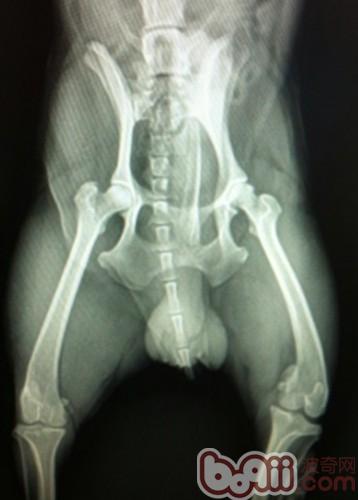

6岁田园犬的髋关节,摆位稍有不正,基本在关节窝内二:全髋骨修复术,指用一个假髋臼杯和股骨组件替换退化的髋关节,常用于保守治疗无效的年轻成犬,手术成功率很高,但这与实施手术医生的经验有很大关系,属于较为复杂的外科手术,需要有经验和训练有序的医生来实施。